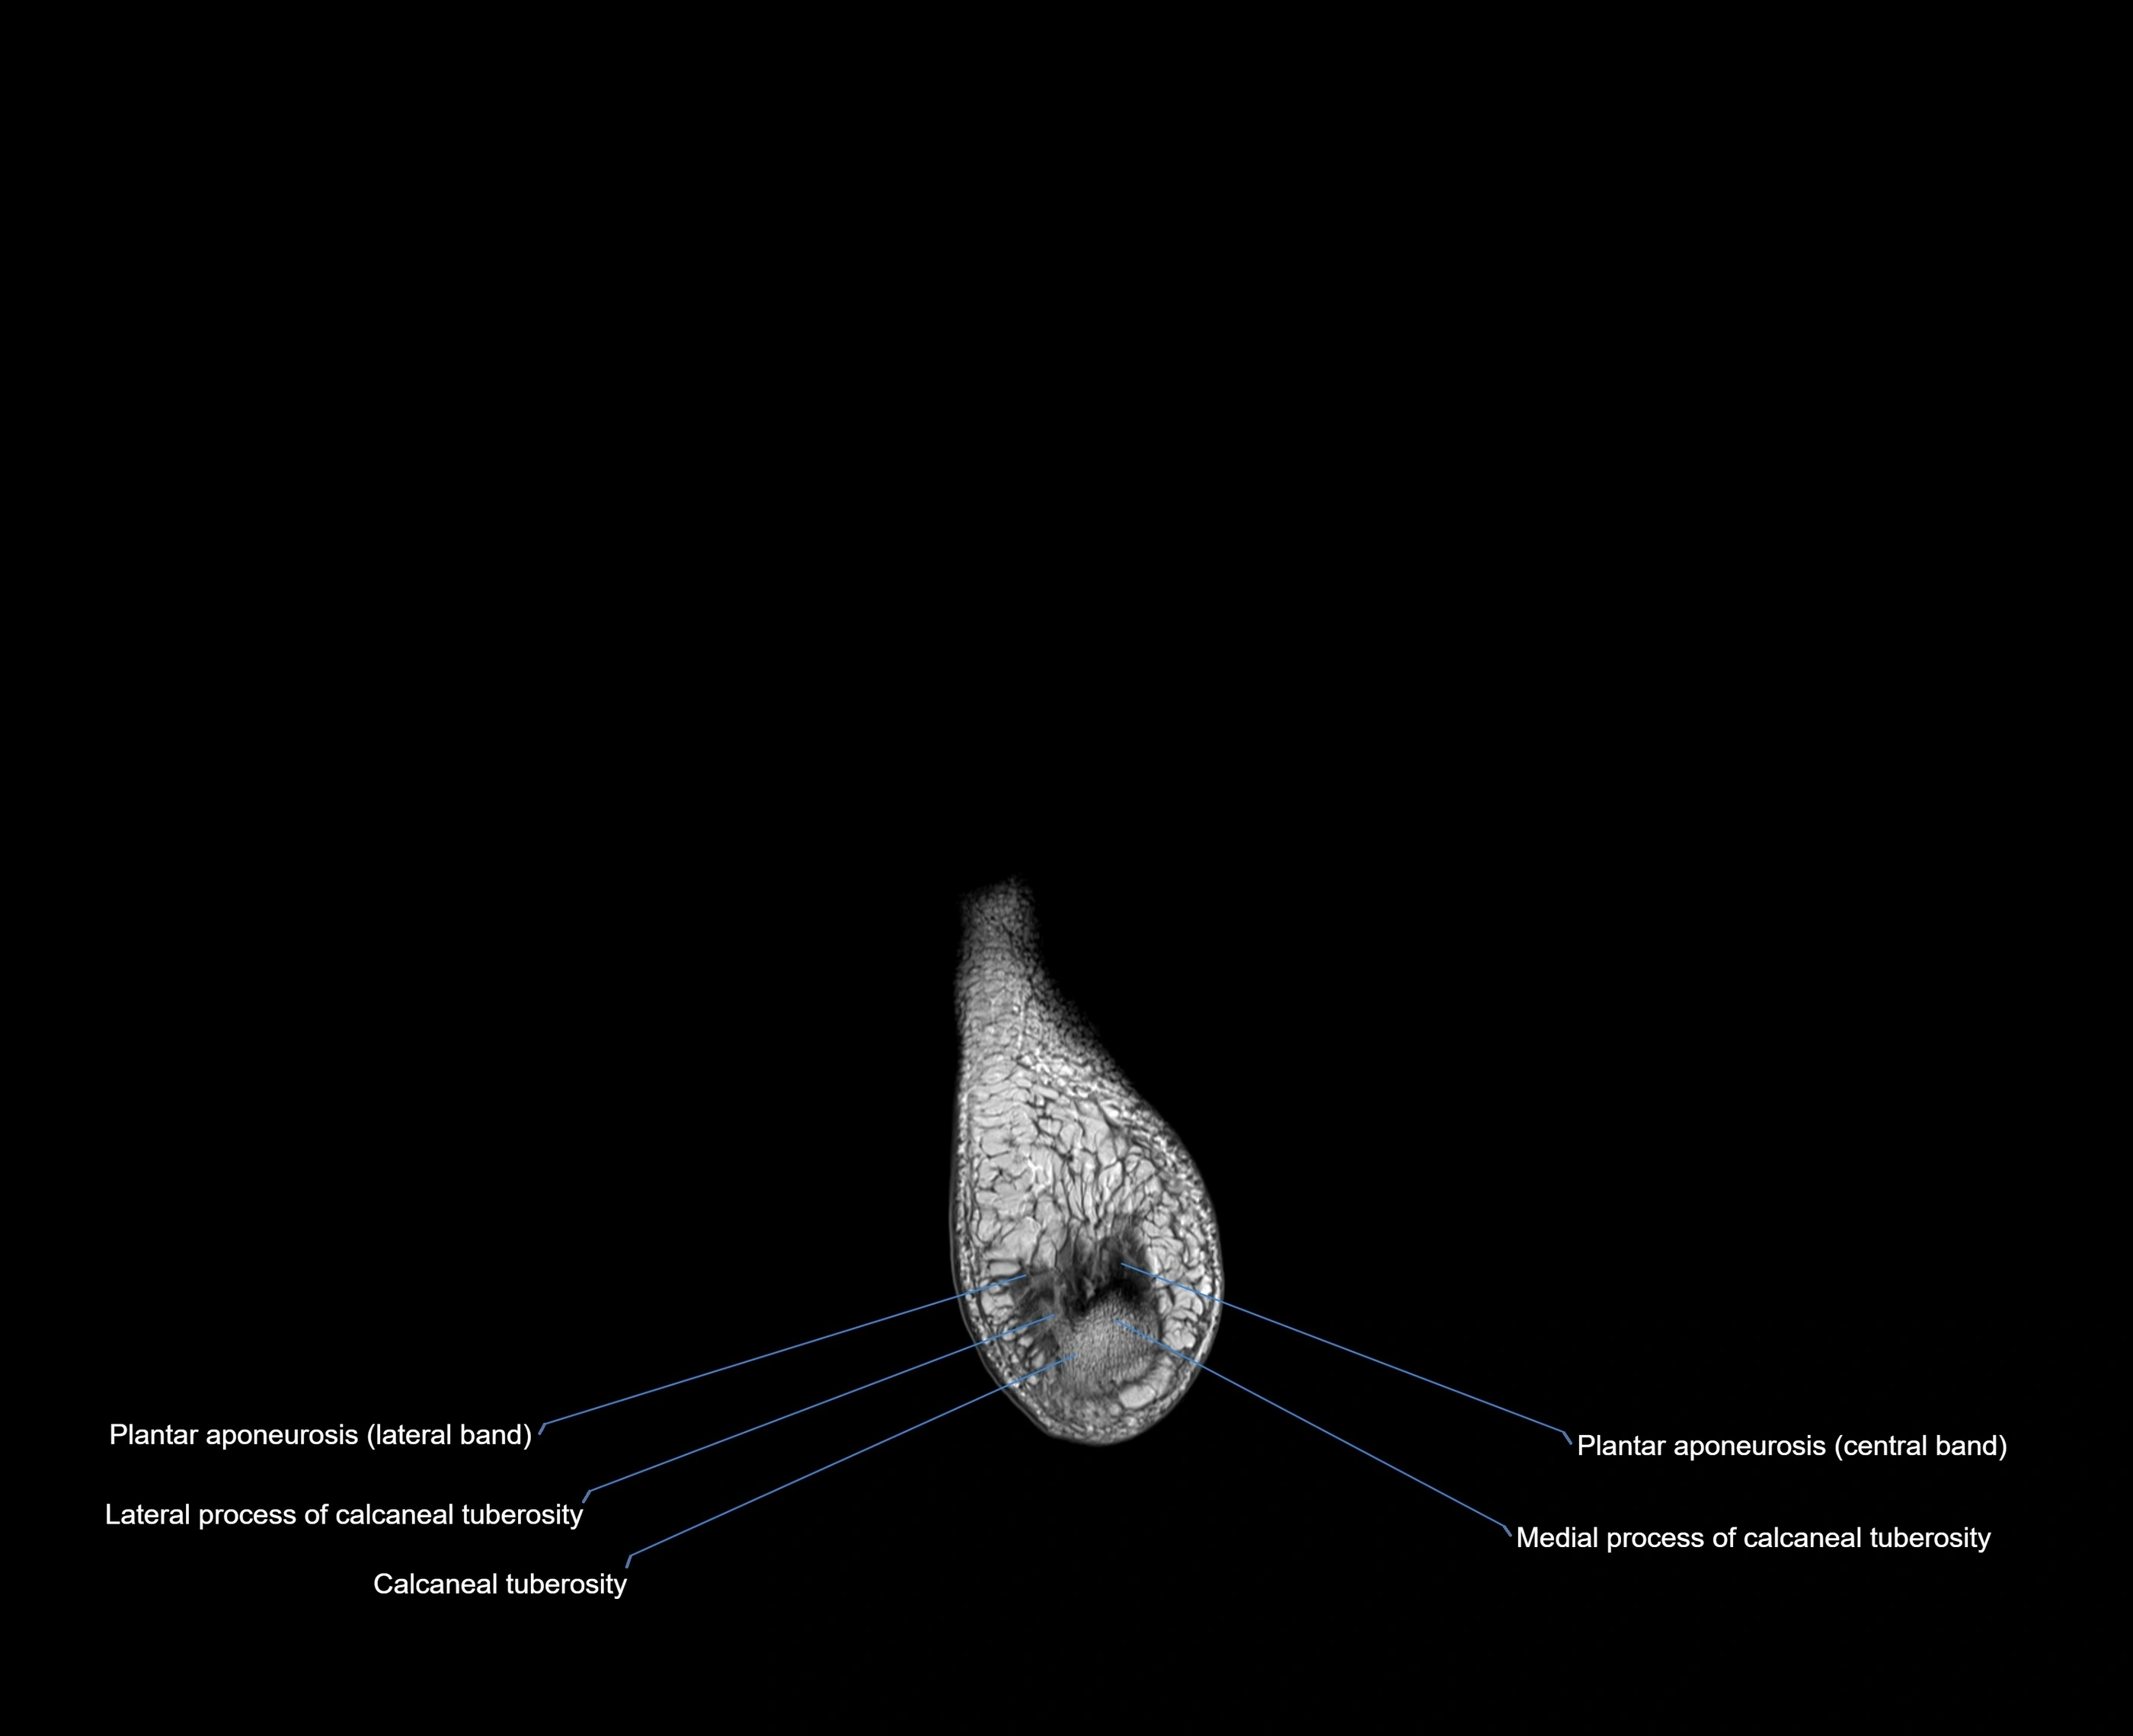

MRI image